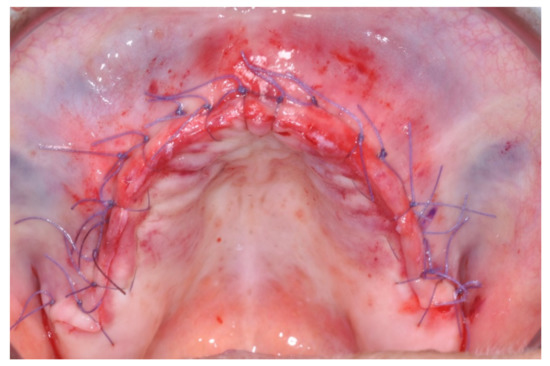

At this point, a non-resorbable high-density PTFE barrier (Cytoplast TXT-200, Osteogenics Biomedical, Lubbock, TX, USA) was designed on the basis of the bone defect shape and was distally blocked on the bone by two titanium pins (Kalos, Nike, Orbetello, Italy). A mixture of 50% autogenous bone harvested from the mandibular ramus with the use of a scraper and 50% inorganic bovine bone (Bio-Oss, Geistlich, Wolhusen, Switzerland) was placed in the recipient site and the membrane was pulled and blocked on the bone with two mesial pins. With this particular, and innovative, non-resorbable membrane management, the graft was compressed and fixed on the recipient bed (Figure 9, Figure 10 and Figure 11). The occlusal portion of the graft was then covered with a layer of a collagen resorbable barrier (Bio-Gide, Geistlich) (Figure 12) and peri-osteal incisions were performed to make the flap passive.

Resorbable sutures (Vicryl 6-0 SH1 needle of 17 mm 1/2c; Ethicon, New Brunswick, NJ, USA) were placed, alternating between single sutures and horizontal mattrass sutures (Figure 13).

Figure 13. After suturing.